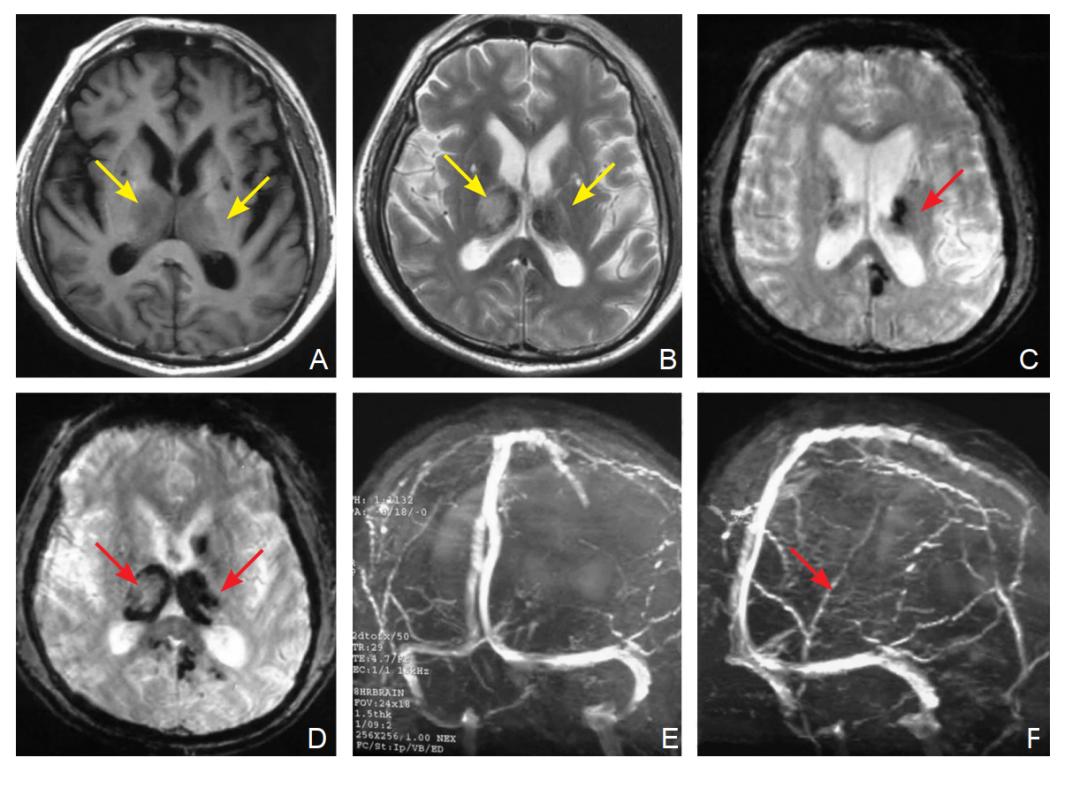

图5 MRI T1序列显示双侧丘脑长T1信号[A],长T2信号、混杂短T2信号,T2*提示双侧丘脑病灶合并内部出血[C,D],MRV提示深静脉不显影[E,F],考虑为深静脉血栓合并双侧丘脑水肿并出血③CTV、MRV、DSA